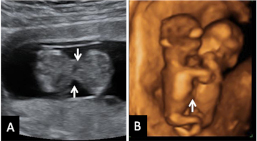

Con la ecografía de la semana 12 de embarazo se pueden detectar algunos signos (marcadores) característicos de los fetos con alguna anomalía cromosómica. Uno de ellos es el ángulo que forman el maxilar superior y el hueso frontal.

Qué mide el ángulo frontomaxilar del bebé

Se mide el ángulo que forman el maxilar superior y el hueso frontal. Los valores están tabulados por semana de embarazo. Cuándo este ángulo es mayor de lo normal, existe mayor riesgo de que ese feto tenga síndrome de Down. Es anormal en aproximadamente el 45% de los fetos con síndrome de Down.